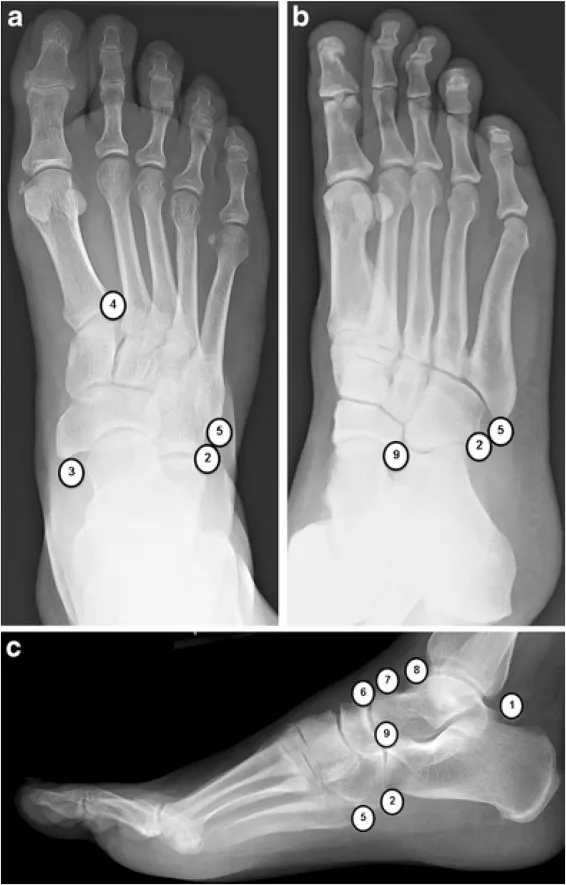

- Accessory Ossicles: Unfused bone centers that mimic fractures. Differentiated by smooth, corticated borders.

- Os Trigonum: Posterior ankle. Pain with plantar flexion (os trigonum syndrome).

- Accessory Navicular: Medial foot. Can lead to painful tendinopathy.